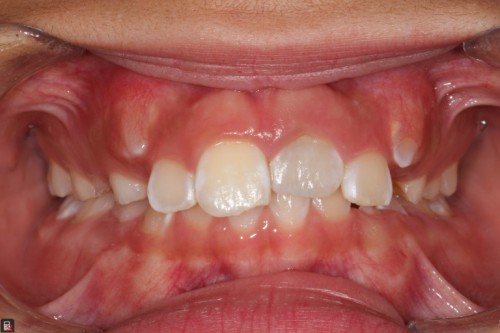

Dens Invaginatus and Regenerative Endodontics on a 7 year old

By Rajiv Patel / August 27, 2018